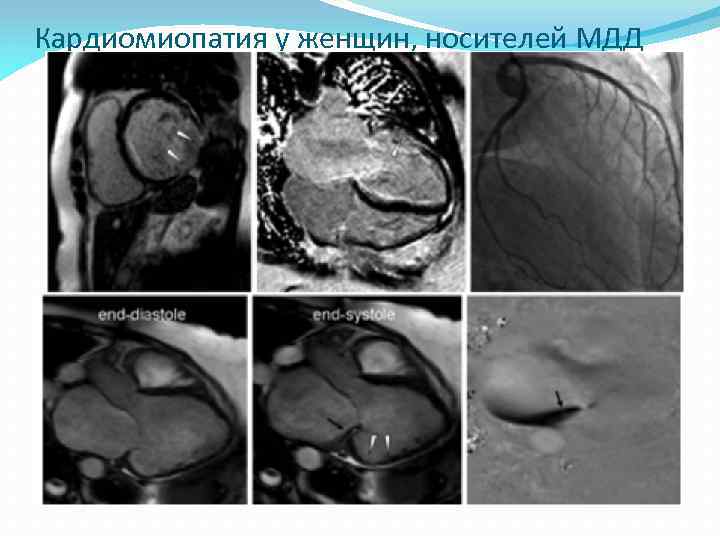

Кардиомиопатия у женщин, носителей МДД